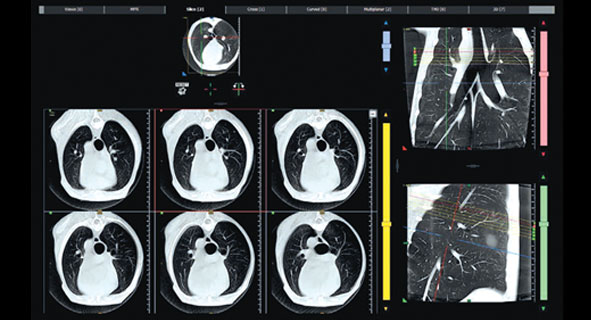

Технология КЛКТ позволяет получать детальные изображения костей с нативными изотропными вокселями, неперекрывающимися срезами и подавлением артефактов.

Устройство генерирует 2D и 3D изображения сверхвысокого разрешения, снижая дозу облучения до десяти раз по сравнению с традиционной компьютерной томографией.